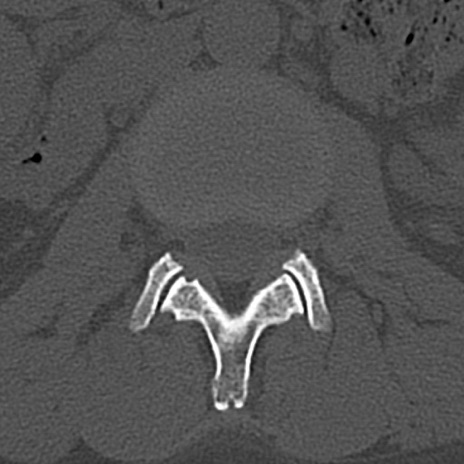

【整形】TIPS症例4 腰椎CT(横断像)

腰椎CT

横断像と矢状断像